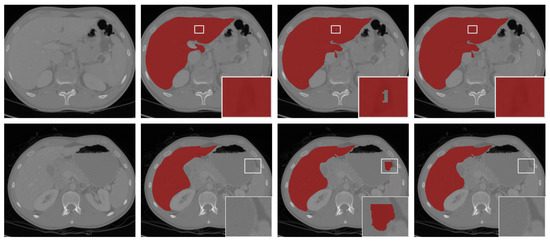

Figure 5 visualizes the prediction results of different networks on two slices of the CHAOS-CT datasets, and it can be clearly observed that the other networks highlighted more over-segmented regions outside the ground-truth compared with our network. Further, we can observe that the results for Bui-Net, DMFNet, HDC-Net, RatLesNetv2, and RSANet showed obvious segmentation noise in the background region. Although 3D ESP-Net did not present this phenomenon, the result showed an obvious “hole” inside of the liver, which was an obvious error-segmentation. However, our approach did not show these evident inaccurate results. In addition, most methods showed over-segmentation or under-segmentation on the boundaries of liver because it is very blurred in the CT image. From the zoom-in results of the first two rows of Figure 5, we can see that all mentioned methods had obvious under-segmentation except HDC-Net and our method, but our method had less noise in the background region. From the zoom-in results of the last two rows in Figure 5, we observe that many methods showed obvious over-segmentation on the liver boundaries. Only our method and 3D ESPNet achieved a good performance in this region, but 3D ESPNet extracted a “hole” in the liver region. In summary, compared to other methods, the boundary results obtained by our method were smoother, and the shape of the liver was more similar to the ground-truth.

Figure 5.

Visualizations (without post-processing) of different methods for liver CT segmentation of two slices. From left to right in the first and third rows: the original images, ground-truth, the segmentation results of skip-connected 3D DenseNet, DMFNet, and HDC-Net, respectively. From left to right in the second and fourth rows: the segmentation results of 3D ESPNet, RatLesNetv2, RSANet, 3D UNet, and 3D FAS-UNet, respectively.

We show visual comparisons before and after post-processing in Figure 6. The results demonstrated that the “hole” (the first row in Figure 6) was effectively filled, and the “island” (the second row in Figure 6) in the background was removed by post-processing. The experiments indicated that our model-driven approach with post-processing was more effective.

Figure 6.

The segmentation results with post-processing. From left to right: the selected scans of the validation set (first column), ground-truths (second column), segmentation results of 3D FAS-UNet without post-processing (third column), and results with post-processing (fourth column).